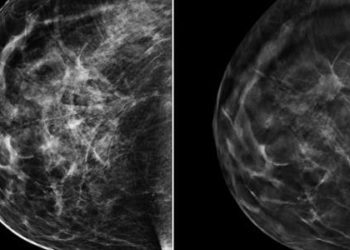

Study Rundown: An aggressive brain tumor with a poor prognosis, glioblastoma multiforme, is typically treated with a combination of surgical resection, chemotherapy, and external beam radiation. Despite multimodal therapy, these tumors frequently recur or progress and must be carefully followed with diagnostic imaging to guide decisions regarding their course of management. Contrast-enhanced MR imaging is currently the standard of care for tumor surveillance, but its performance is limited by post-treatment changes to the tumor bed. Specifically, increased MR contrast enhancement may be due either to true tumor progression or to benign, treatment-related inflammation, a phenomenon termed pseudoprogression. Features previously suggested to indicate true progression include a reduced apparent diffusion coefficient, increased cerebral blood volume, and a subependymal enhancement pattern, but none of these findings alone is sufficiently sensitive or specific to confidently register a diagnosis.

The current study sought to expand upon the available techniques used to identify true progression by utilizing calculated pharmacokinetic parameters of tissue permeability derived from contrast-enhanced MR-images. Among patients with treated glioblastoma, one pharmacokinetic value, the volume transfer coefficient (Ktrans), was found to be highly specific and moderately sensitive for true progression when increased. This finding was theorized to represent the increased neoplastic vascular burden or increased blood-brain permeability in the tumor bed among patients with progression of their disease. The study was limited by a small sample size and the lack of a comparison to standard imaging modalities used for the evaluation of tumor progression. Further studies incorporating traditional MR and diffusion-weighted imaging are warranted to examine the cumulative predictive effect.

In-Depth [prospective cohort]: Thirty-three patients with pathology-proven glioblastoma multiforme and new enhancing lesions within the tumor bed following surgical resection, external beam radiation, and temozolomide chemotherapy were examined using contrast-enhanced MRI with quantitative perfusion analysis. Using this technique, pharmacokinetic parameters such as Ktrans (volume transfer constant), ve (extravascular extracellular space) and vp (plasma blood volume per unit volume of tissue) were calculated for each patient. The presence or absence of true disease progression was determined by the Response Assessment in Neuro-Oncology (RANO) criteria, which specify a set of contrast-enhanced imaging findings that define true progression and pseudoprogression 12 weeks following completion of glioblastoma treatment. Quantitative MR imaging parameters were then compared to the RANO reference standard to determine the diagnostic performance of quantitative MR imaging in the diagnosis of true progression. Mean Ktrans was significantly elevated in the 17 patients exhibiting true progression versus the psuedoprogression group (P = 0.004), and mean ve was also significantly elevated in the true progression group (P = 0.034). Mean vp did not differ between the two groups (P > 0.05). Of these values, only an elevation of mean Ktrans beyond a threshold value of 0.347 min-1 was strongly predictive of tumor progression, with a sensitivity of 59% and a specificity of 94%.